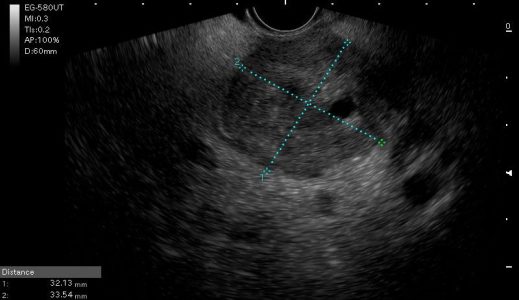

Ο Ενδοσκοπικός υπέρηχος πραγματοποιείται με τη χρήση ειδικών ενδοσκοπίων τα οποία διαθέτουν κεφαλή υπερήχων ενσωματωμένη στο άκρο τους. Ανάλογα με την ένδειξη επιλέγεται το πιο κατάλληλο ενδοσκόπιο (radial ή linear). Η διαφορά των δύο ενδοσκοπίων έγκειται στον τρόπο λήψης της υπερηχοτομογραφικής εικόνας αλλά και στη δυνατότητα ή όχι λήψης ιστολογικού υλικού (linear).

Για το λόγο αυτό τα τελευταία χρόνια χρησιμοποιούνται σχεδόν αποκλειστικά τα linear ηχοενδοσκόπια. Μέσω ειδικού επεξεργαστή αναπαράγονται υπερηχοτομογραφικές εικόνες ενώ μέσω του συστήματος  Doppler είναι δυνατή η ανίχνευση της ροής του αίματος και συνεπώς ο εντοπισμός αγγειακών δομών με αποτέλεσμα να είναι δυνατή η ασφαλής στόχευση για παρακέντηση όγκων ή κυστικών αλλοιώσεων.

Εξάλλου, με τη χρήση ειδικών λογισμικών είναι δυνατή η διενέργεια ελαστογραφίας καθώς και υπερήχου με χρήση σκιαστικών ουσιών με σκοπό την πληρέστερη απεικόνιση των σημείων ενδιαφέροντος. Οι  λεπτές βελόνες που χρησιμοποιούνται για τη λήψη κυτταρολογικού ή ιστολογικού υλικού, προσαρμόζονται στο ενδοσκόπιο και μέσω ειδικού καναλιού που διαθέτει το ενδοσκόπιο προωθούνται στο σημείο ενδιαφέροντος.